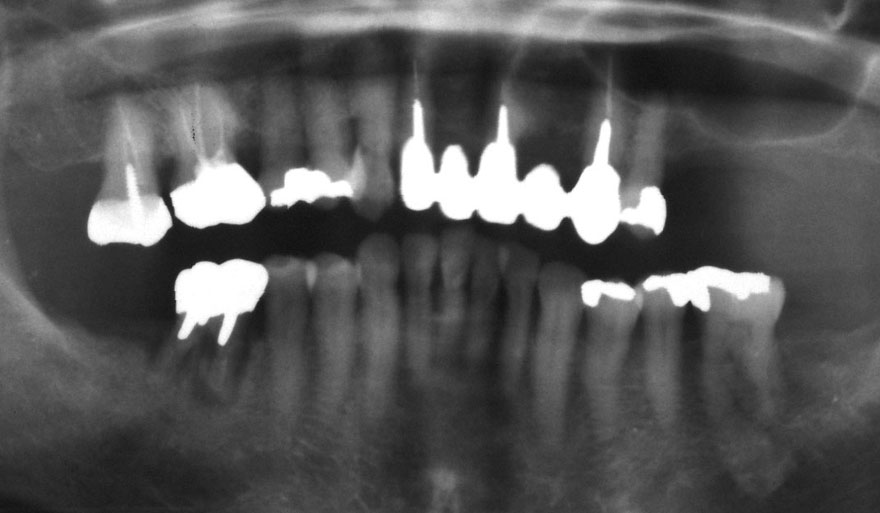

初診時 41歳 男性 平均歯槽骨喪失量:4.11mm

30年後 71歳

平均歯槽骨喪失量:3.70mm

30年間再生量:+0.41mm

年間再生速度:+0.014mm

(ケア頻度:1.27ヵ月ごと)